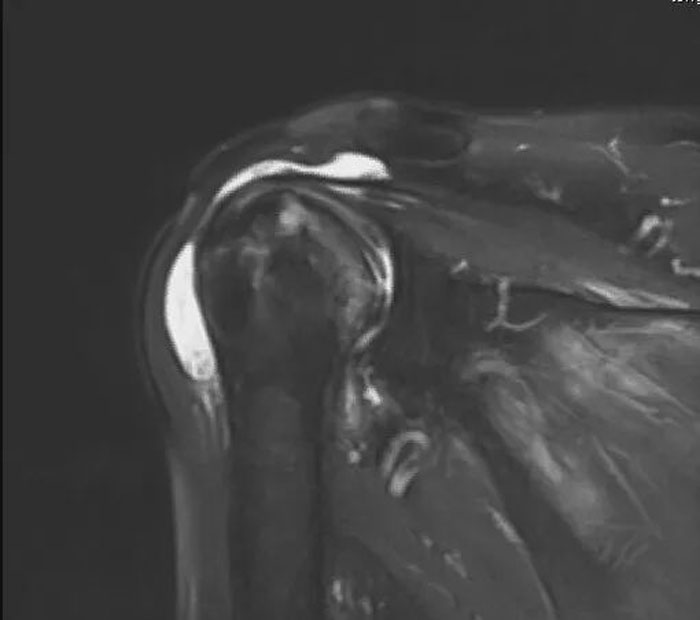

肩關(guān)節(jié)是人體所有關(guān)節(jié)中活動(dòng)量最大、最靈活的一個(gè)關(guān)節(jié),任何損傷都會(huì)讓患者“飽受肩熬”。本例患者賀大爺肩關(guān)節(jié)疼痛數(shù)月,夜間疼痛嚴(yán)重,影響睡眠,肩關(guān)節(jié)活動(dòng)明顯受限,行磁共振檢查提示肱骨頭壞死并肩袖損傷??盗⑿轮魅吾t(yī)師在考慮患者病情、影像學(xué)檢查、風(fēng)險(xiǎn)評(píng)估、術(shù)后獲益以及患者和家屬意愿的基礎(chǔ)上,建議患者行反式人工全肩關(guān)節(jié)置換術(shù),重建患者肩關(guān)節(jié)。

術(shù)前